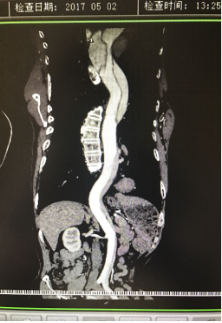

5月2號(hào)劉大伯照常早起干活,突然胸部劇烈疼痛,難以忍受,全身大汗,同時(shí)伴有右上肢發(fā)涼,他心想這次心絞痛比之前嚴(yán)重的多啊,趕緊叫上孩子到吉林國(guó)文醫(yī)院心血管內(nèi)科住院,患者長(zhǎng)期高血壓病史,血壓一直控制不理想,大夫給他做了檢查,測(cè)左上肢血壓:82/45mmHg,右上肢血壓測(cè)不出,心率52次/分,右側(cè)肱動(dòng)脈、尺動(dòng)脈、橈動(dòng)脈搏動(dòng)消失,左側(cè)股動(dòng)脈搏動(dòng)較右側(cè)弱?!霸懔?,雙側(cè)血壓差別這么大,是不是主動(dòng)脈夾層了?”,接診大夫趕緊找來(lái)李主任,李主任反復(fù)詢(xún)問(wèn)患者病情,表情突然凝重起來(lái),患者胸痛這么明顯,血壓低的厲害,主動(dòng)脈夾層的可能性很大。二話不說(shuō),李主任立即聯(lián)系影像科的醫(yī)生準(zhǔn)備做主動(dòng)脈CTA,移動(dòng)患者做檢查的過(guò)程大夫們非常小心,嚴(yán)密監(jiān)測(cè)患者血壓變化情況。兩個(gè)小時(shí)后結(jié)果出來(lái)了,主動(dòng)脈夾層從升主動(dòng)脈一直撕裂到左側(cè)髂總動(dòng)脈?。?!

從開(kāi)始學(xué)醫(yī)到現(xiàn)在已經(jīng)快9年了,主動(dòng)脈夾層患者也見(jiàn)過(guò)一些,但像劉大伯這種危險(xiǎn)類(lèi)型的還是第一次見(jiàn)到,心里真的為他捏把汗,撕裂的主動(dòng)脈隨時(shí)都有可能破裂,生命隨時(shí)可能終止,要知道主動(dòng)脈夾層的死亡率非常的高,約50%的患者發(fā)病后48小時(shí)死亡,約90%的患者發(fā)病1個(gè)月內(nèi)死亡。